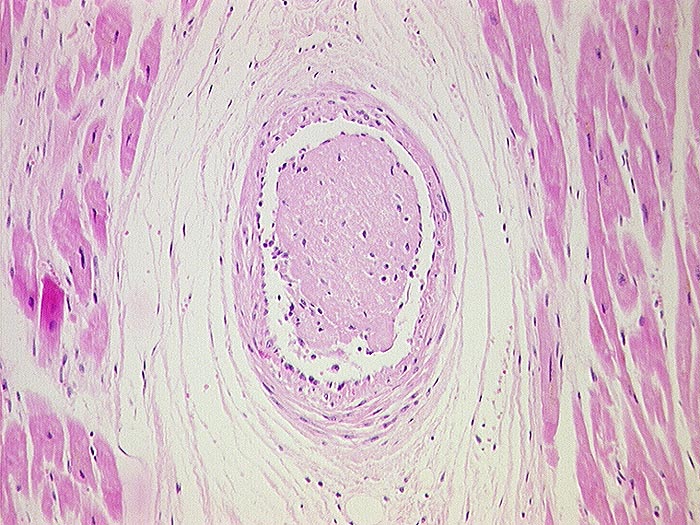

Koronarembolie bei Endocarditis marantica

In einem intramyokardialen arteriellen Gefäss liegt ein frischer Fibrinthrombus, der sich aus der Vegetation (Fibrin!) einer Endocarditis marantica gelöst hat.

non bacterial thrombotic endocarditis

Endocarditis marantica bei Tumorleiden. Todesursache ist ein koronarembolischer Myokardinfarkt.